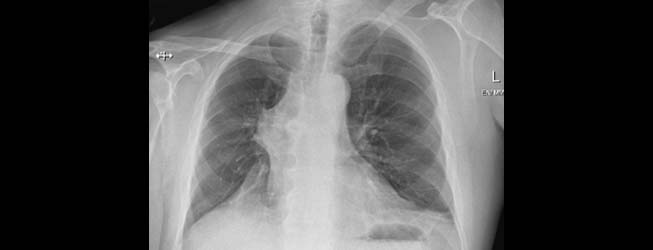

History: a 75 year old man status post partial left upper lobectomy, complicated by pneumothoraces status post chest tube placemente, presented with diffuse crepitus.

A chest radiograph was performed and is shown below. Radiographs: Diffuse subcutaneous emphysema and pneumomediastinum. Patchy basilar opacities In keeping with atelectasis and a probable small amount of left pleural fluid. Small biapical pneumothoraces

Chest CT: Extensive postoperative subcutaneous emphysema and pneumomediastinum. There is a moderate left-sided pneumothorax after left upper partial lobectomy, despite the presence o left chest tube with its lip at the left ape

Diagnosis: latrogenic subcutaneous emphysema